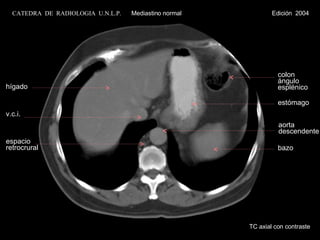

TC axial concontraste hígado v.c.i. espacio retrocrural colon ángulo esplénico estómago bazo aorta descendente CATEDRA DE RADIOLOGIA U.N.L.P. Mediastino normal Edición 2004

TC axial con contraste hígado v.c.i. espacio retrocrural colon ángulo esplénico estómago bazo aorta descendente CATEDRA  DE  RADIOLOGIA  U.N.L.P.   Mediastino normal  Edición  2004